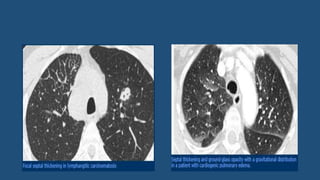

Thickening of interlobular septa

• Perilymphatic area

• Peripheral part of the secundary lobule.

• It is usually the site of diseases, that are located in the lymphatics of in the

interlobular septa ( i.e. sarcoid, lymphangitic carcinomatosis, pulmonary

edema).